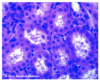

Simple Cuboidal Epithelium

Simple Cuboidal Epithelium